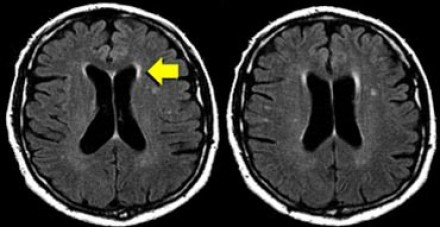

圖片十一

上圖是該患者冠狀位釓增強T1加權(quán)成像圖像。請仔細觀察上圖,我們可以看到在基底節(jié)中有點狀增強病灶,這種病灶特征可見于肉樣瘤,也可見于系統(tǒng)性紅斑狼瘡或其他血管炎性疾病。

該病例中,肉樣瘤的典型特征是軟腦膜增強(黃色箭頭所示),這是由軟腦膜發(fā)生肉芽腫性炎癥造成的。

圖片十二

該患者的另一個典型特征是線性增強病灶(上圖中黃色箭頭所示),這是由于沿著血管周圍間隙發(fā)生炎癥病變造成的,也是另一種形式的軟腦膜增強。

這些特征也就解釋了為什么肉樣瘤的病灶特征會與MS相似:血管周圍間隙與MS病變累及的小穿透靜脈相似。